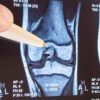

The primary outcome measure was active ROM which was measured using a 12” universal goniometer in a standardized procedure with the participant seated in a chair. A photographic record and measure were also taken using the Hudl Ubersense smartphone app (Agile Sports Technologies, Lincoln, Nebraska, USA) (see Figure 3). A recent study has found the app to have high levels of concurrent validity and intra-rater reliability demonstrating a mean 0.80° difference in a study comparing 40 knee measurements to the gold standard measuring instrument the electrogoniometer.38 Naylor et al’s (2011)39 evidence based standardized method for identifying bony landmarks was employed, including marking the distal flare of the lateral malleolus, the centre of rotation of the knee and the proximal flare of the greater trochanter. The assessor visually checked the knee joint was in the sagittal plane ensuring a 2D image was photographed. The same physiotherapist (SKA) recorded all ROM measurements for each patient, angles were randomly double checked by a blinded third-party clinician.